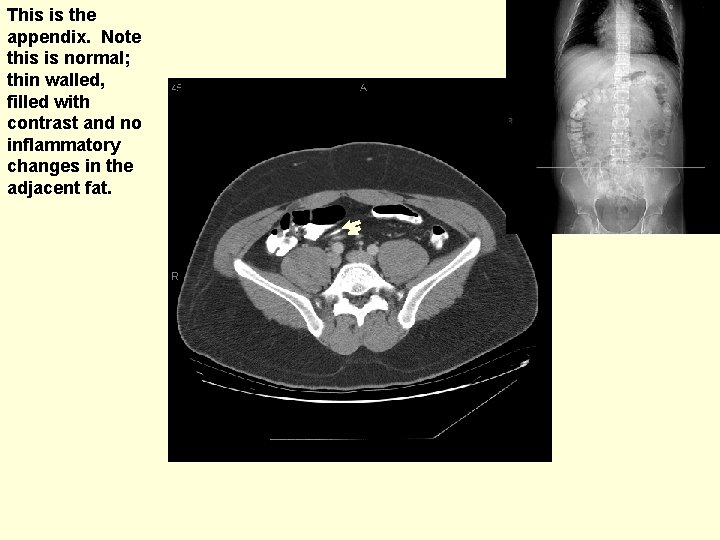

What is this small tubular structure partially filled with contrast on this and the subsequent image. (see next slide for answer)

This is the appendix. Note this is normal; thin walled, filled with contrast and no inflammatory changes in the adjacent fat.